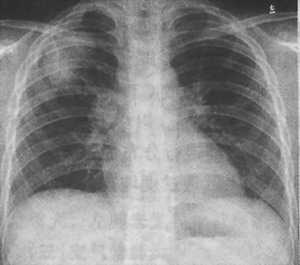

同时,结核杆菌还会沿着淋巴管通向靠近肺门的淋巴结,导致淋巴结肿大,这又叫原发性肺结核。临床上主要表现为咳嗽、周身不适、倦怠、午后低热、盗汗、体重减轻等症状。如果上述症状持续时间较长而没有特殊原因者,可能为肺结核早期症状,其胸片特异表现为“哑铃征”。

△原发性肺结核“哑铃”状胸片,箭头所指为结核初发病灶(图片来源:life.yxlady.com)